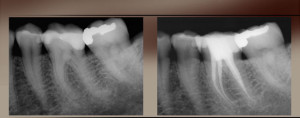

Perpunimi kimik dhe fizik i kanaleve ,behet me instrumenta te posacem dhe me materiale te ndryshme ne varesi te patologjise se nervit te dhembit .Zakonisht dhembet qe i nenshtrohen trajtimit endodontik ,kerkojne me shume se nje seance per tu trajtuar.Vetem atehere kur mjeku eshte i bindur se perpunim i kanalit eshte kryer sic duhet,nuk ka me mbetje apo mikroorganizma ne kanal apo perreth rrenjes ,pacienti nuk ka me  dhimbje,dhe ne grafi kontrolli shikohet eleminimi i proceseve periapikale,atehere kanali eshte gati per tu mbushur.Ne kliniken tone perdoren materiale te firmes

dhimbje,dhe ne grafi kontrolli shikohet eleminimi i proceseve periapikale,atehere kanali eshte gati per tu mbushur.Ne kliniken tone perdoren materiale te firmes